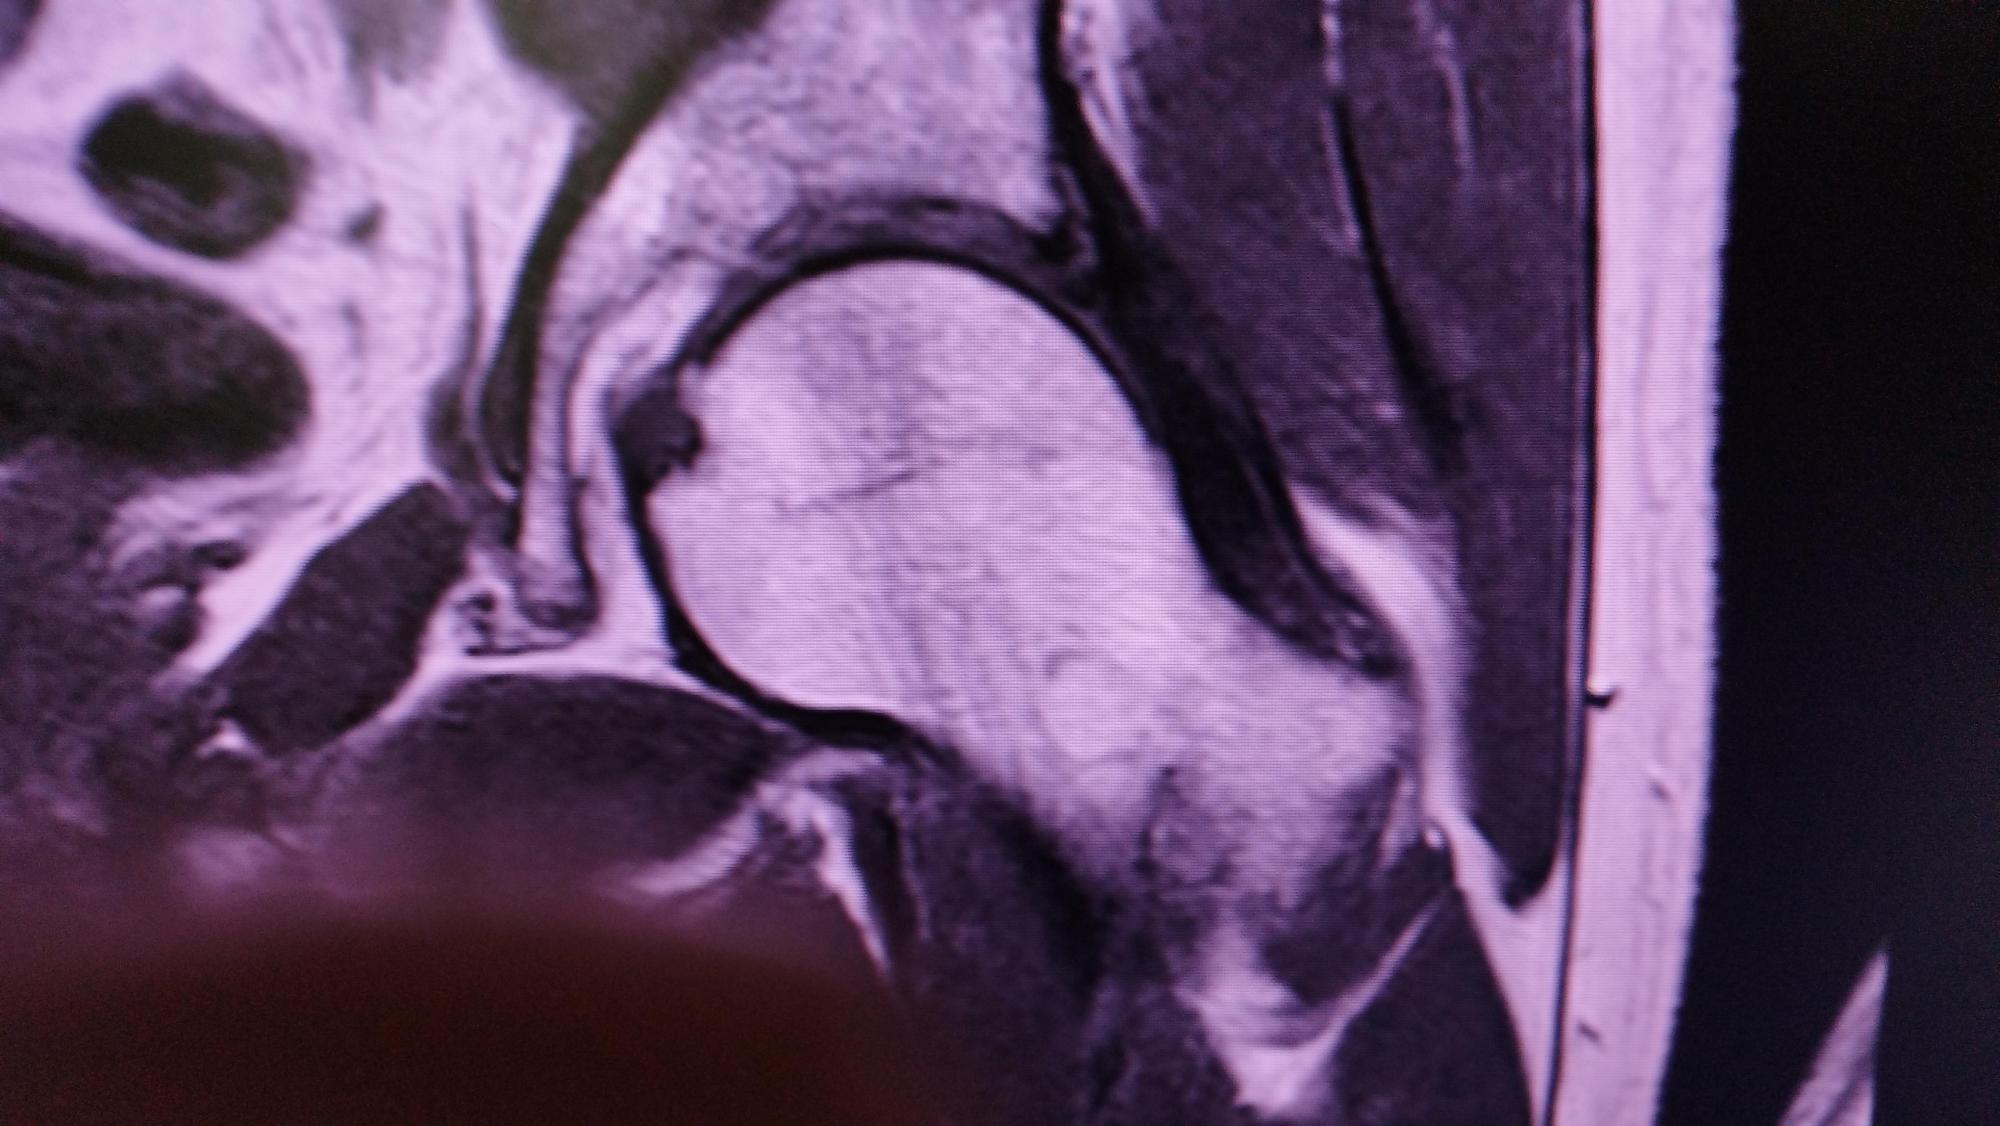

Hier die Ergebnisse des ersten MRT:

Keine Arthrose. Verdacht auf eine kleine Labrumläsion, Geringer Reizzustand am Kapselligament. Geringer Reizzustand am linken ISG. Ich war dann

erstmal etwas beruhigter.

Hier die Ergebnisse des zweiten MRT:

Beidseits Zeichen eines Pinzer CAM-Impingements. Gelenkspalt beidseitig kranial leicht verringert. Ganglion am Ansatz des Labrums ohne Nachweis

auf Rissbildung. Geringe Insertionstendiopatie.

Berichte beider MRTs und Bilder aus dem ersten MRT im Anhang

IMG_20240408_152407.jpg

IMG_20240408_152424.jpg